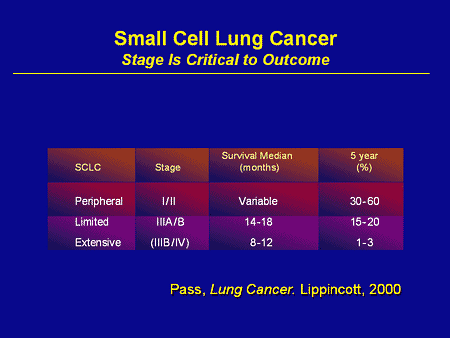

Small Cell Lung Cancer (SCLC) Much less common, small cell lung cancer encompasses approximately 10 to 15 percent of patients with the disease. This type of lung cancer grows and spreads much more aggressively and is already metastasized to distant regions of the body in 70 percent of related diagnoses. Additionally, it mostly affects smokers.